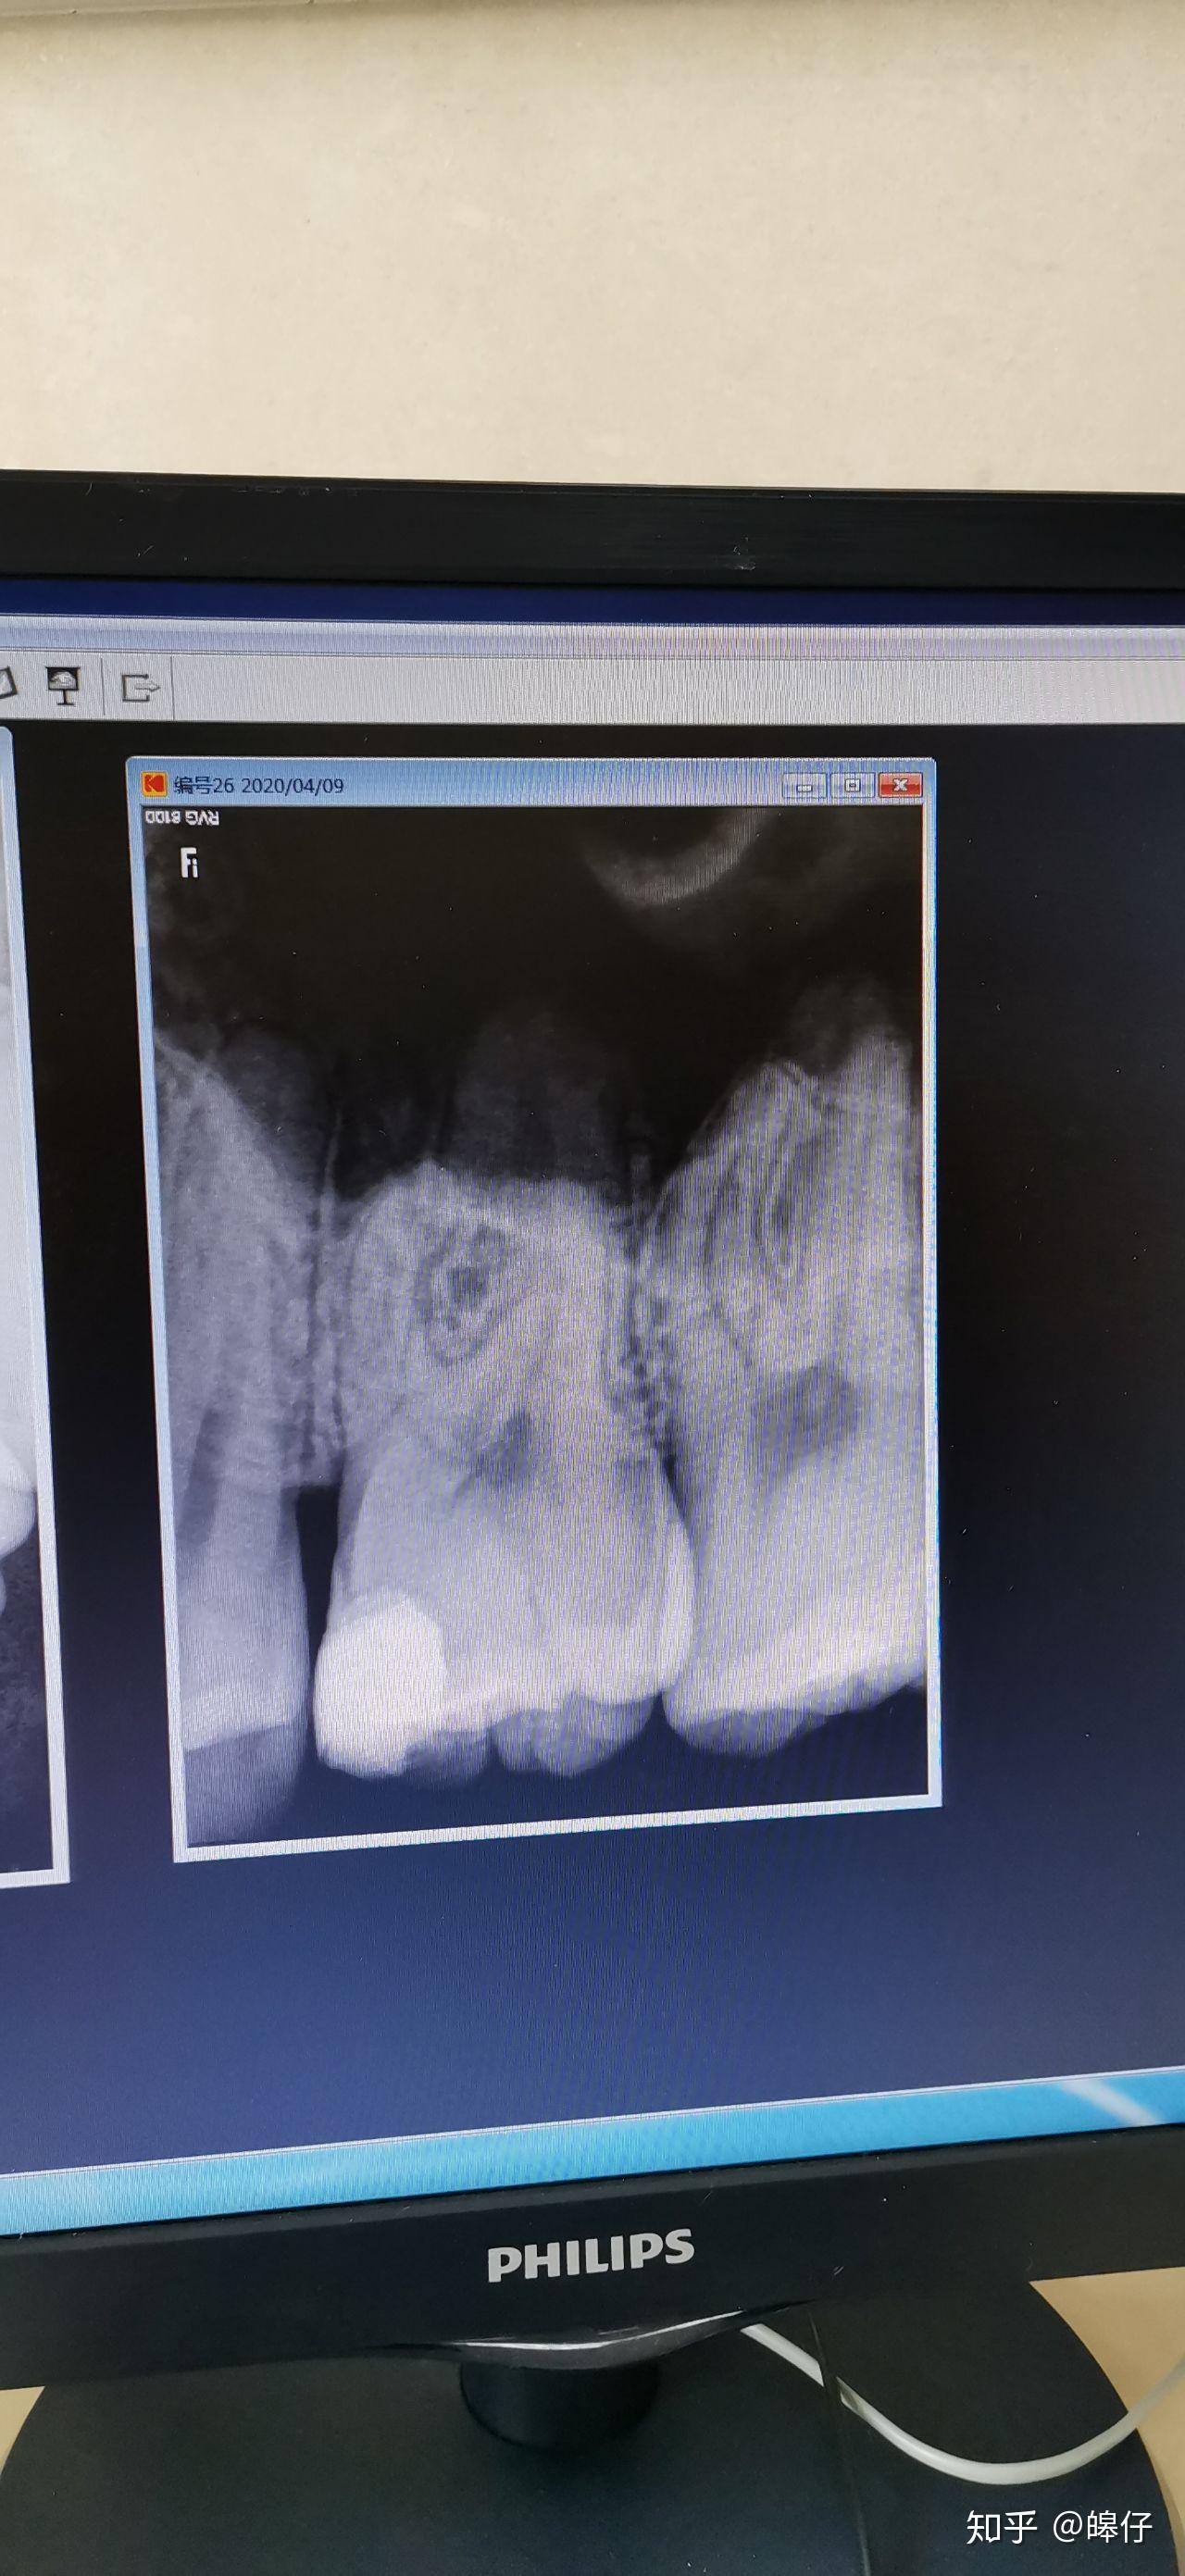

查体 辅查 36远中临面大面积龋坏,x线片可见远中龋坏深入髓腔,根尖

松动1-2度,可探及根分叉病变,牙龈红肿,bop( ),x线片示深龋坏近髓,根